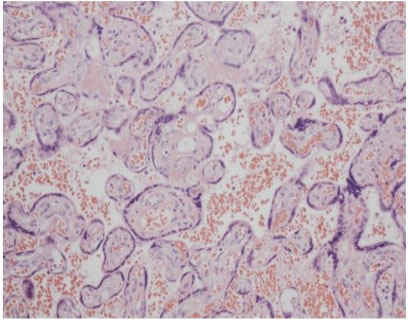

This is a case of a 26-year-old now G1P0104 woman with three years of anovulatory infertility. She became pregnant through controlled ovarian stimulation at the completion of her third cycle of clomiphene citrate and the pregnancy resulted in quadruplets. She had a prolonged history of symptomatic uterine contractions resulting in a hospitalization from 26 to 31 weeks. However, she underwent urgent cesarean delivery due to non-reassuring biophysical profile of one of the quadruplets. She was delivered of four live neonates; three females and one male. The placenta retrieved (Figure 1) showed widespread Tenney-Parker changes upon histologic examination. Figure 2 depicts the widespread Tenney-Parker changes in the retrieved placenta, but Figure 3 shows a normal placenta histology for comparison. Multifetal pregnancies are often associated with increased pregnancy complications, adverse perinatal outcomes, and increased maternal morbidity. Women with multifetal pregnancy are 6 times more likely to have a premature delivery and 13 times more likely to deliver before 32 weeks [4]. There is also an increased risk of short- and long-term neonatal and infant morbidity associated with multifetal gestations.

Figure 2: Pathological slide of the placenta retrieved showing widespread Tenney-Parker changes exemplified by the syncytial knots at the edges of the syncytiotrophoblasts. Hematoxylin and Eosin stain, 200× magnification.